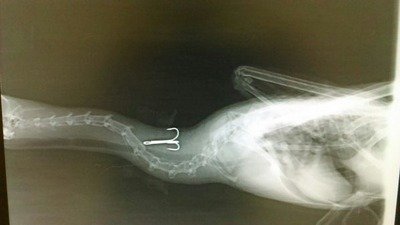

La Urbanización Parquelagos se encuentra situada en un lugar privilegiado, en su interior se encuentra La Presa de Los Rosales, que por no estar calificada, se entiende que es responsabilidad del Ayuntamiento del Termino Municipal a que corresponde, en este caso Galapagar. Han sido censadas mas de 137 especies de aves muchas de ellas que pasan el invierno en este maravilloso enclave, que constituye un hábitat idóneo para su alimentación e incluso su época de cría. Se han observado aves protegidas como Aguila Imperial bebiendo agua en sus orillas, Porrones, Cormoranes incluso especies de difícil observación como Tarro canelo, Cigüeña negra etc. El problema real son los pseupescadores, que además de llenar sus orillas con acampadas prohibidas, ensucian abandonando incluso artes de pesca, convirtiendo la zona en un basurero peligroso para la fauna e incluso también para los vecinos.